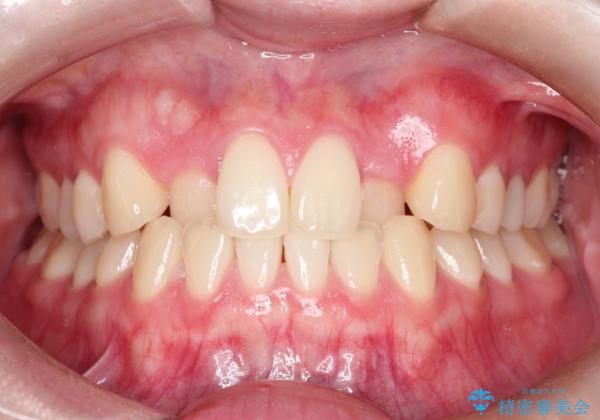

インビザラインとワイヤー矯正の併用で綺麗な歯並びに!

- 前歯のガタツキが気になるとのことで来院されました。

ワイヤー矯正とインビザライン矯正を併用することによって、治療期間の短縮と、より良い仕上がりを目指す治療を選択することとしました。

インビザライン(アライナー)矯正とワイヤー矯正のそれぞれの利点を生かした治療を行い、綺麗な歯並びになりました。